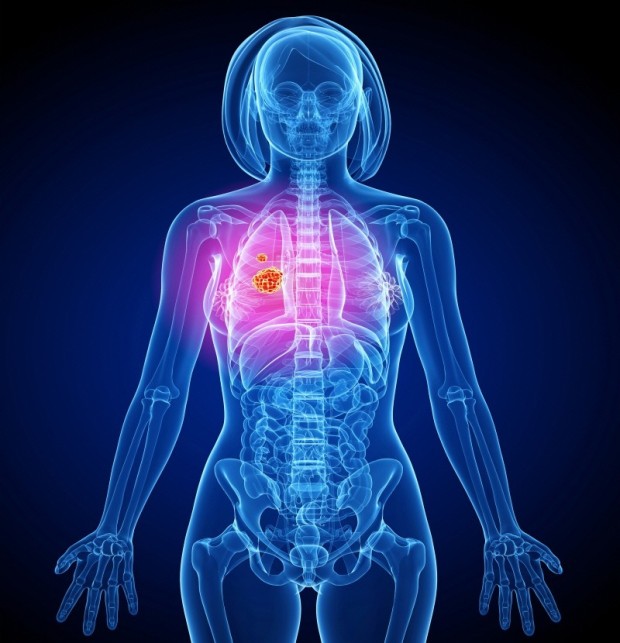

오늘은 우리 몸의 호흡을 책임지는 폐에 대해 이야기하려 합니다. 특히, 폐에 발생하는 악성 종양인 폐암의 초기 증상에 대해 자세히 알아보려 합니다.

폐암 초기에는 특별한 증상이 없는 경우가 많지만, 암이 진행되면서 다양한 신호를 보낼 수 있습니다. 다음은 폐암 환자들이 흔히 경험하는 10가지 주요 초기 증상입니다.

오늘 함께 알아본 폐암 초기 증상들이 여러분의 건강 관리에 큰 도움이 되었으면 합니다. 폐암은 조기에 발견하면 완치율이 높은 암이므로, 자신의 몸에 나타나는 작은 신호에도 귀 기울이는 습관을 들이는 것이 중요합니다. 오늘 알려드린 내용을 바탕으로 자신의 건강을 체크하고, 궁금한 점이 있다면 언제든지 전문 의료진과 상담하는 것을 잊지 마세요. 우리 모두 건강한 삶을 위해 노력해요!